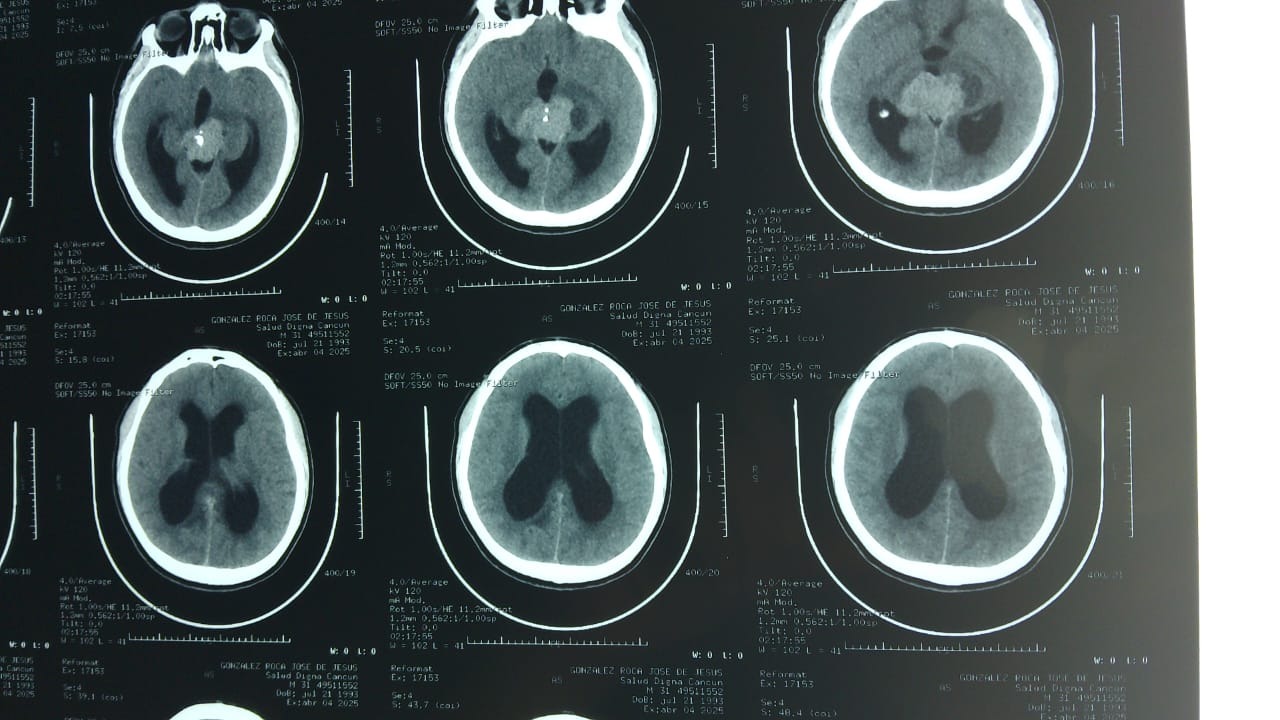

Hola, me llamo José de Jesús, tengo 32 años y vivo en Cancún, México. En abril de este año me detectaron un tumor cerebral en la glándula pineal, el cual se ha ido tratando poco a poco en el Instituto Mexicano del Seguro Social. Afortunadamente, con los estudios previos se determinó que es operable. Lamentablemente no se podrá programar en Mérida (que es lo más cercano geográficamente) hasta dentro de 6 meses más o menos, lo cual implica un riesgo de que se siga desarrollando y mi salud se vea más comprometida. Por esta razón nos vamos a ir a la CDMX para buscar otras opciones; una de las que tenemos al momento es operar con un neurocirujano particular por 100K (en pesos mexicanos) lamentablemente no contamos con esa cantidad por lo que creamos este perfil esperando tener su apoyo en la recaudación. Muchas gracias

Hello, my name is José de Jesús, I am 32 years old and I live in Cancún, Mexico. In April of this year, I was diagnosed with a brain tumor in the pineal gland, which has been treated gradually at the Mexican Social Security Institute (IMSS). Fortunately, previous tests determined that it is operable. Unfortunately, surgery cannot be scheduled in Mérida (which is the closest city geographically) for about six months, which means there is a risk that the tumor will continue to grow and my health will be further compromised. For this reason, we are going to Mexico City to look for other options; one of the options we have at the moment is surgery with a private neurosurgeon for 100,000 (Mexican pesos). Unfortunately, we don't have that amount, so we created this profile hoping to have your support in fundraising. Thank you very much.